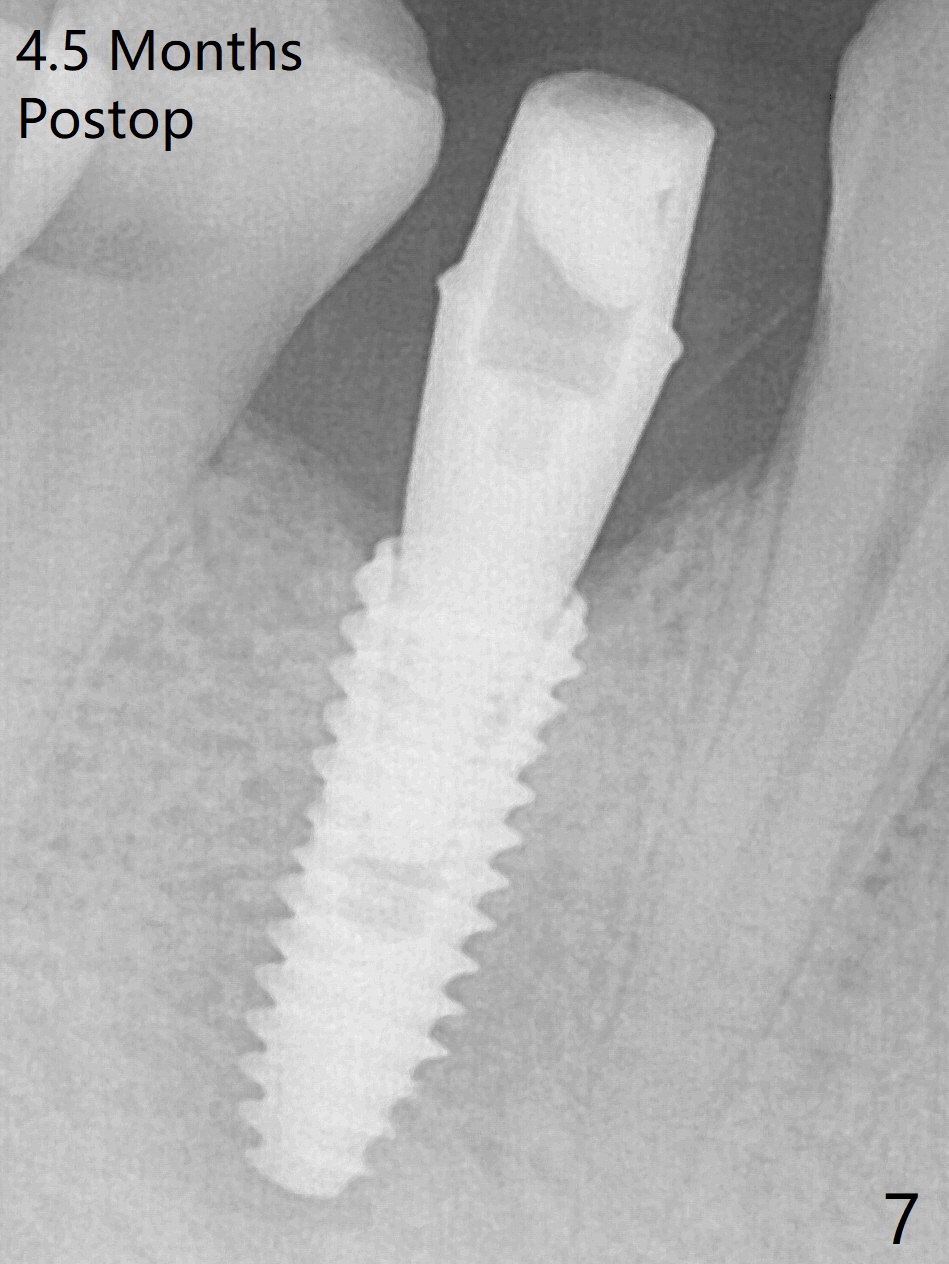

Immediately post extraction and curettage of the large buccal apical lesion, osteotomy is established in the lingual wall of the socket of #28 (slightly distal) for 17 mm vs. 15 mm socket depth (Fig.1 (red line: Mental Loop)). Following sequential osteotomy until 3.5x17 mm drill, a 4x10 mm dummy implant is partially placed with stability (Fig.2,3 (root measurement: mesiodistal 4 mm; buccolingual 7 mm)). A final implant (4x11.5 mm) is placed with insertion torque of 60 Ncm (Fig.4,5). Since the buccal crest is lower with the buccal gingival recession, the implant is intentionally placed deep as well as lingually so that autogenous bone and Vera graft mixture will be placed in the buccal gap (Fig.6 * (gauze at the moment)). The apical lesion decreases 4.5 months postop (Fig.7). Immediate implant and immediate provisional keep the papillae (Fig.8 *), but cannot prevent the buccal plate from atrophy (Fig.9 *). It appears that socket shield is able to accomplish the latter. The bone density next to the coronal threads increases 10 months post cementation (Fig.10 *) and seems to have continued to do so 1 year 4 months post cementation (Fig.11).